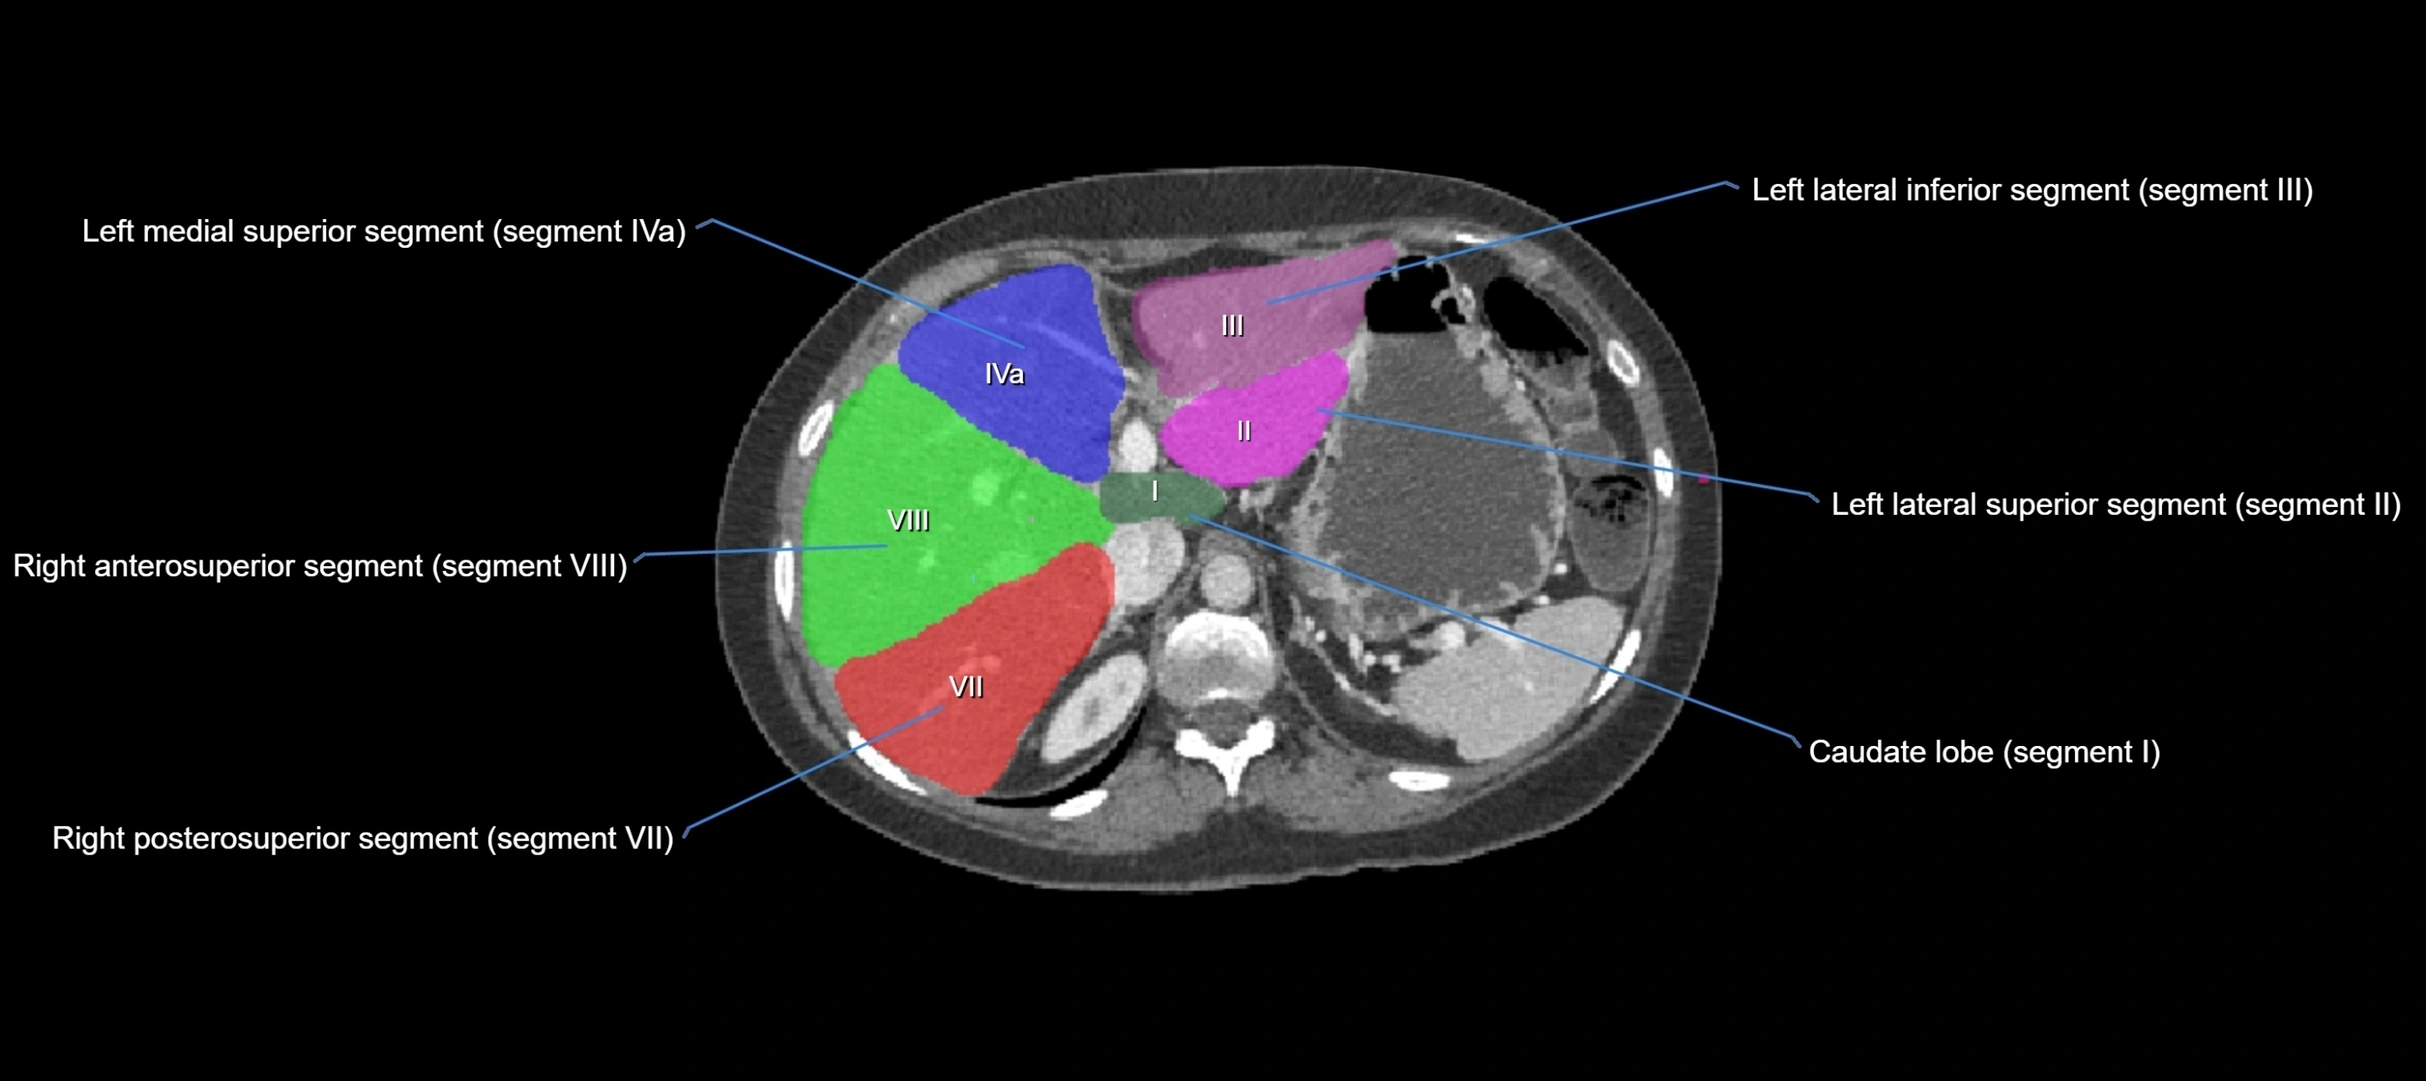

The caudate lobe of the liver is a distinct anatomical subdivision of the liver, designated as segment I in Couinaud’s classification. It lies on the posterior surface of the liver, between the fissure for the ligamentum venosum (left boundary) and the groove for the inferior vena cava (IVC) (right boundary). Superiorly, it is related to the posterior liver surface, and inferiorly it is separated from the left lobe by the porta hepatis.

The caudate lobe is unique because it receives dual portal venous and arterial inflow from both the right and left portal veins and hepatic arteries. It also has independent venous drainage directly into the IVC via multiple small hepatic veins, unlike other lobes that drain through the three main hepatic veins.

• Segment I (Couinaud classification)